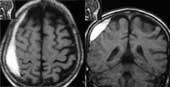

Рис. 3. Подострая стадия субарахноидального кровоизлияния - очаги организации крови (стрелки) в проекции межполушарных и конвекситальных субарахноидальных пространств. (Слева) Т1 режим. (Справа) Т2 режим.